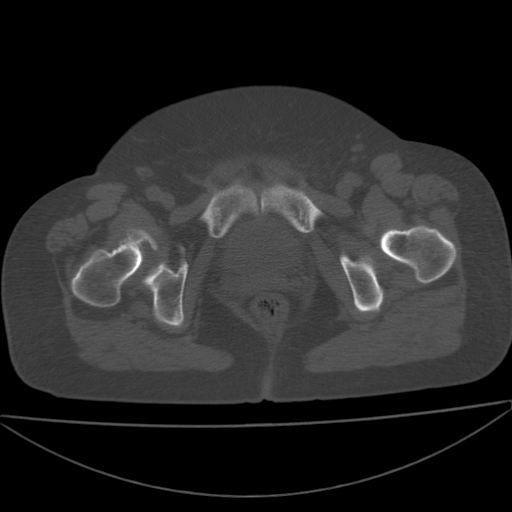

以下是引用余辉在2009-4-23 17:08:00的发言:[br]考虑右髋关节退行性变.股骨颈改变考虑陈旧性骨折可能,股骨头顶部关节面下似有透亮区,股骨头皮质环增厚,考虑有股骨头坏死

以下是引用王显瑞在2009-4-23 16:45:00的发言:[br]考虑股骨颈陈旧性骨折,股骨头缺血型坏死